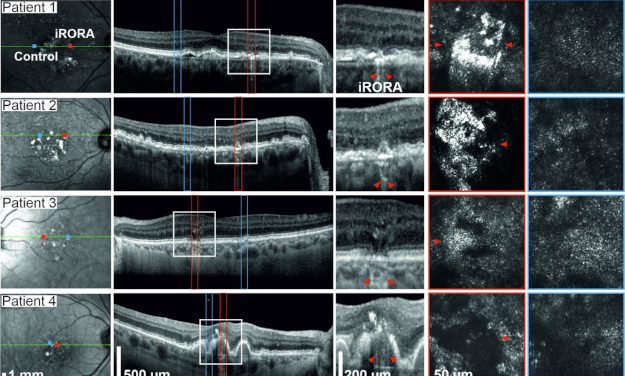

Leer másNuevos biomarcadores de la atrofia geográfica

1 Sep, 2023 | Atrofia Geográfica, DMAE Degeneración Macular

Nuevos biomarcadores de la atrofia geográfica La imagen multimodal es ahora la norma para...